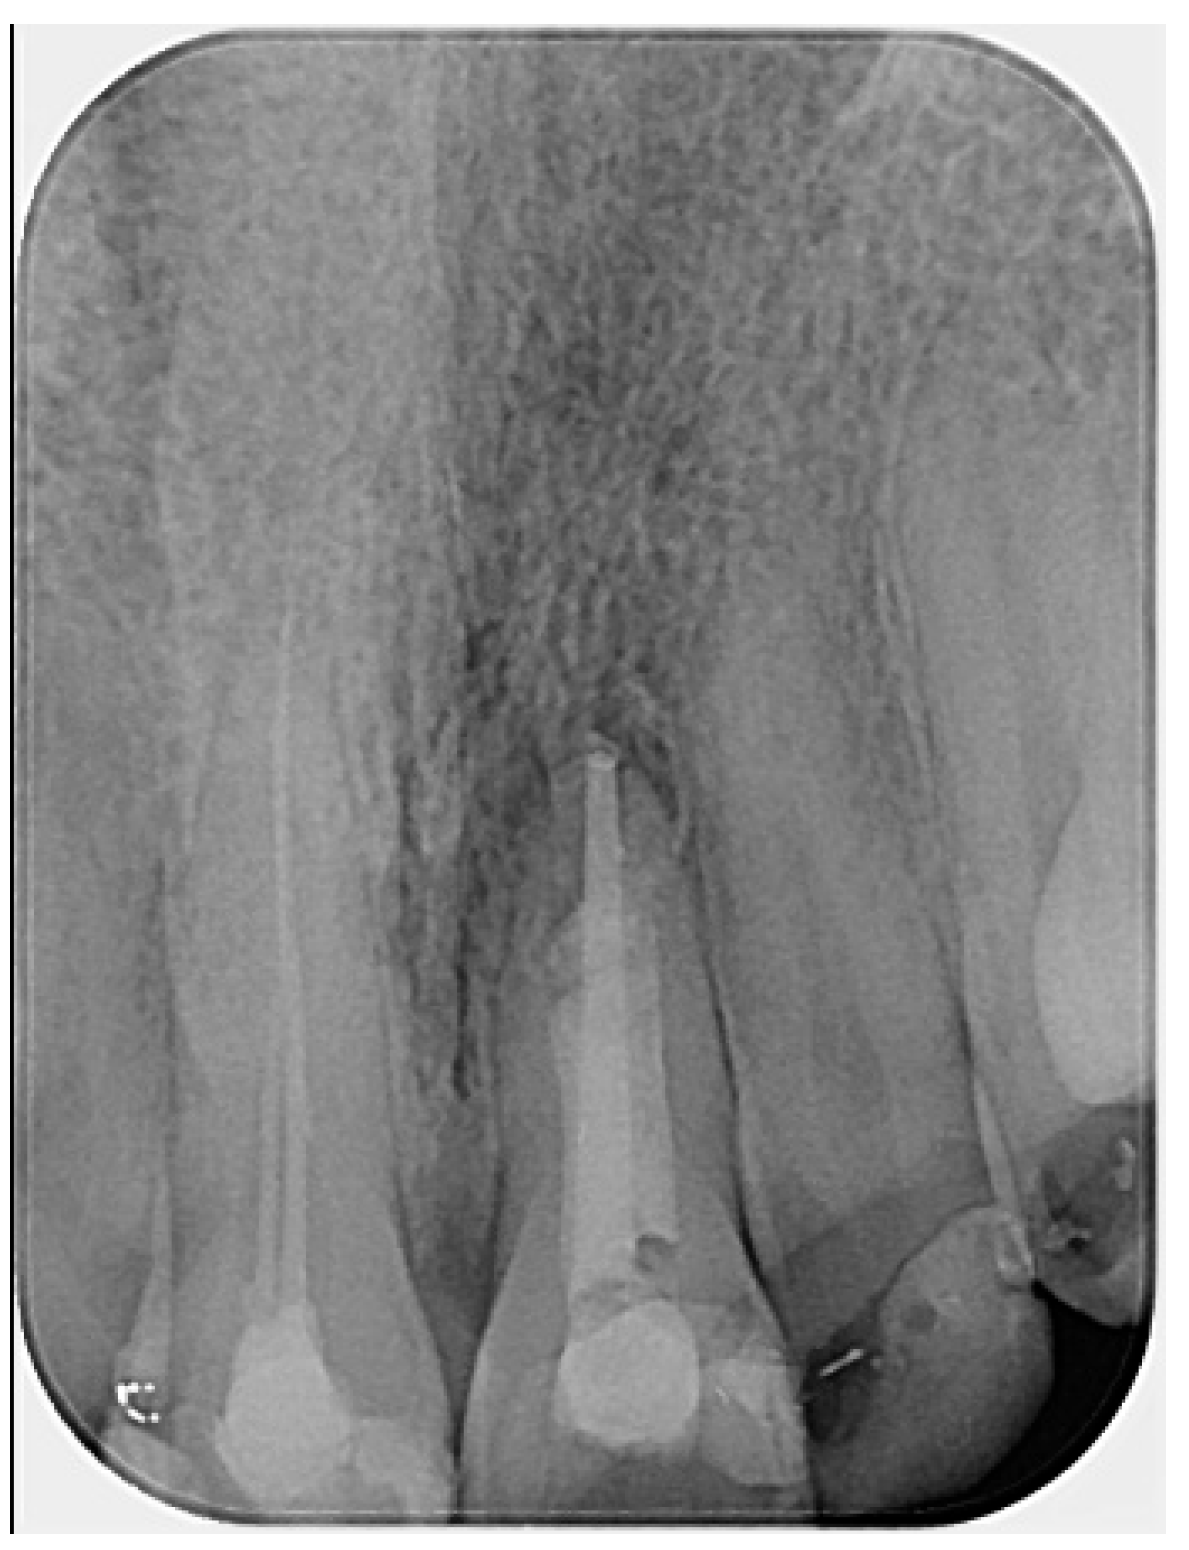

Figure 5. Complete regeneration of the apical bone fenestration observed over a period of two years and eight months: (a) periapical radiograph showing resolution of the periapical radiolucency; (b) CBCT scan confirming re-establishment of the cortical bone and healthy periapical tissues; (c) the 3D reconstruction is included to illustrate the anatomical changes before and after treatment.

The patient returned for a follow-up visit two years later. The tooth was asymptomatic, and the radiograph showed no signs of periapical radiolucency (Figure 5a). The caries lesion on the mesial surface was treated. Eight months later, a new CBCT scan was performed by another dentist due to a traumatic injury on the right side of the jaw. Upon reviewing the scan, valuable diagnostic information became apparent, including complete restoration of the cortical bone, reestablishment of healthy periapical tissues, and the absence of any radiolucency around the apex of tooth #21. The CBCT PAI score was recorded as 0, indicating complete healing (Figure 5b,c).

Successful treatment at the two-year follow-up was confirmed through clinical examination, absence of patient complaints, and a periapical radiograph. Despite the diagnostic advantages of CBCT, it is not recommended as a routine imaging method for follow-up, even in limited field-of-view settings, in order to minimize patient radiation exposure [14,30]. However, eight months later, the patient experienced a traumatic injury to the right frontal facial region, and a CBCT scan was performed by another clinician. Under these circumstances, it became possible to observe and confirm three-dimensional healing of the lesion, as well as reconstruction of the buccal cortical bone plate, indicating closure of the fenestration. These findings, also visible on the periapical radiograph, support the effectiveness of the non-surgical endodontic treatment approach in cases of bone fenestration.